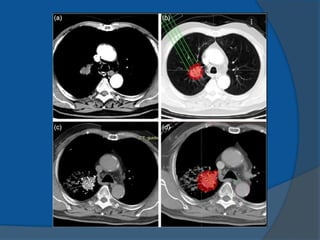

⦿ Brachytherapy (Curietherapy) is defined as a

short-distance treatment of malignant

disease with radiation emanating from small

sealed (encapsulated) sources.

⦿ The sources are placed directly into the

treatment volume or near the treatment

volume

• Improved localized dose delivery to the

target

• Sharp dose fall-off outside the target

• Better conformal therapy